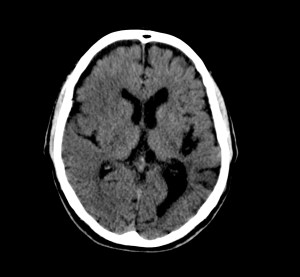

Pues bien, ante los hallazgos descritos, se clarifica que estamos ante un paciente el cual no tiene una masa y que ha sufrido una lesión isquémica hace diez días. Ahora, sobre dicha lesión, tenemos una imagen con un aumento de densidad que sugiere sangrado por una parte y otra hipodensidad en la perifería que correspondería a un edema. Por tanto, descartamos un sangrado intraparenquimatoso de novo. El paciente tiene más de 65 años, no es hipertenso, la imagen del sangrado no es de alta densidad, lo que se opone a una fase aguda o hiperaguda, y tenemos el TC de cráneo previo donde ya se advertía un proceso de tipo isquémico. Por tanto, nos quedan dos opciones, o estamos ante un resangrado de un ACV o estamos ante una Perfusión de lujo.

Vistos los tiempos en los que puede acontecer cada proceso y la atenuación radiológica que se obtiene con la TAC, puede ser dificil distinguir un ACV con transformación hemorrágica, sobre todo si está más evolucionado, de una perfusión de lujo. Necesitaríamos establecer un cronograma radiológico, donde observásemos la evolución de la sangre. En nuestro caso, dadas la evolución y la correlación con la imagen, nos orientaríamos más hacia una perfusión de lujo.